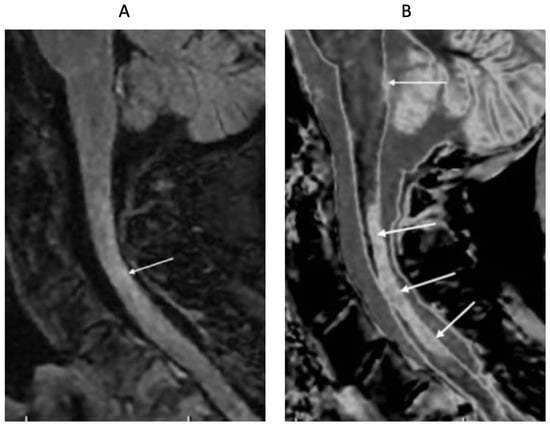

Figure 15 shows T2-FLAIR (Figure 15A) and wide mD dSIR (Figure 15B) sagittal images of the upper cervical spinal cord in a 43-year-old female patient with MS in remission. The T2-FLAIR image shows a poorly defined smudge of increased signal (white arrow). In the corresponding position, the dSIR image (Figure 15B) shows a high-contrast lesion with sharply defined boundaries, which is much more extensive than in (Figure 15A) (lower three arrows). An additional lesion is seen in the medulla on the dSIR image (highest arrow), but is not seen on the T2-FLAIR image.

Figure 15.

Forty-three-year-old female patient with MS in remission. Sagittal 3D T2-FLAIR (A) and 3D wide mD dSIR (B) images. The T2-FLAIR image shows a poorly defined area of increased signal in the cervical cord (arrow). The dSIR image shows a high contrast lesion with sharply defined boundaries, which is much more extensive than in (A) (lower three arrows). An additional lesion is seen in the medulla on the dSIR image (highest arrow) (B), but not on the T2-FLAIR image.

Figure 16 shows the upper cervical spinal cord in a 42-year-old female patient with MS in remission. T2-FLAIR (Figure 16A), T2-wSE (Figure 16B), and wide mD dSIR (Figure 16C) images are compared. A large lesion is seen on all three images, but with greatest contrast on the dSIR image (long white arrows). In addition, three small lesions are only seen on the dSIR image (Figure 16C, short white arrows).

Figure 16.

Forty-two-year-old female patient with MS in remission. Sagittal T2-FLAIR (A), T2-wSE (B), and wide mD dSIR (C) images. A large lesion is seen on all three images but with higher contrast on the dSIR image (long arrows). Three small lesions are only seen on the dSIR image (short arrows).